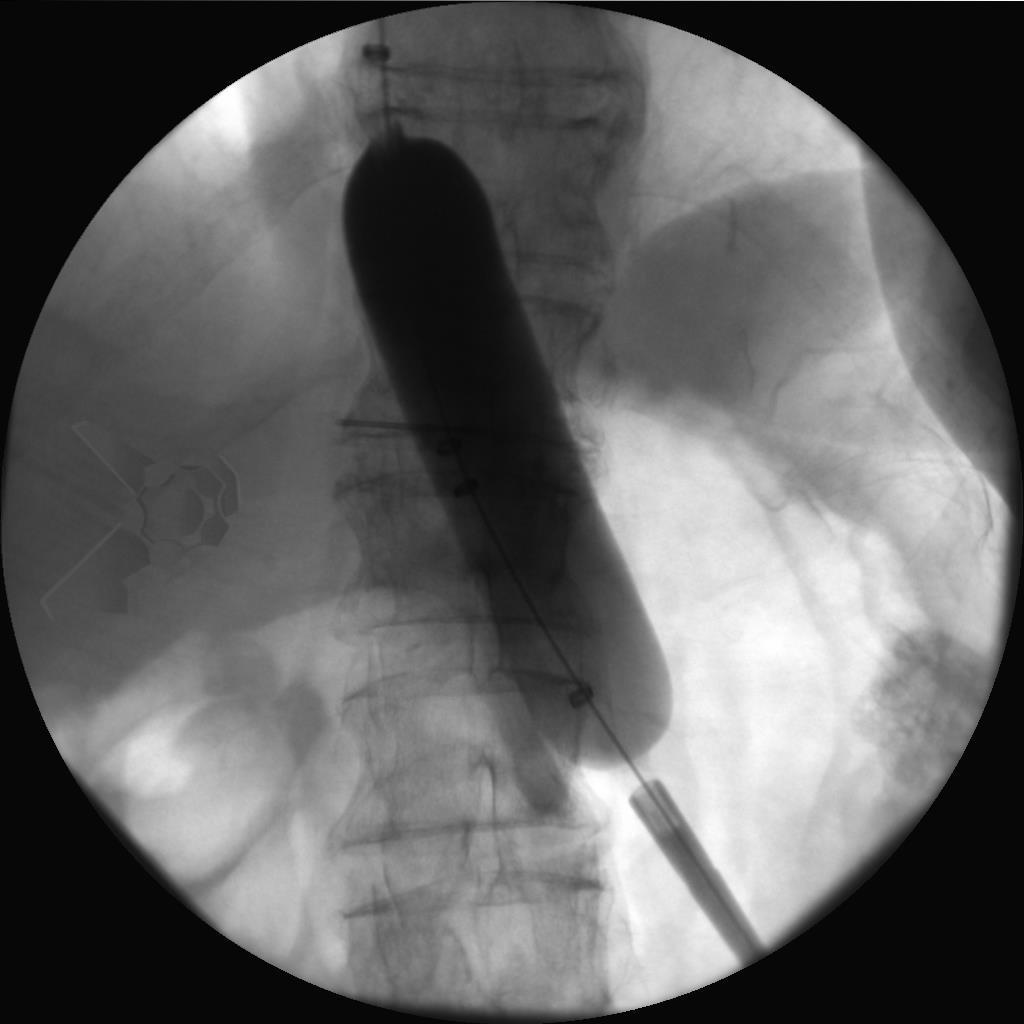

- DP: dilatação para 30 mm, seguida de 35 mm após 1-3 semanas para todos os pacientes. Se os sintomas persistissem após 3 meses, uma DP para 40 mm era realizada. DP de 35 ou 40 mm adicionais ou fora do prazo estipulado poderiam ser realizadas conforme a recorrência dos sintomas, sendo consideradas falhas de tratamento (indicadas com escore de Eckardt >3). Uso de inibidor de bomba de prótons em dose única por 2 semanas após cada dilatação (Fig. 1).